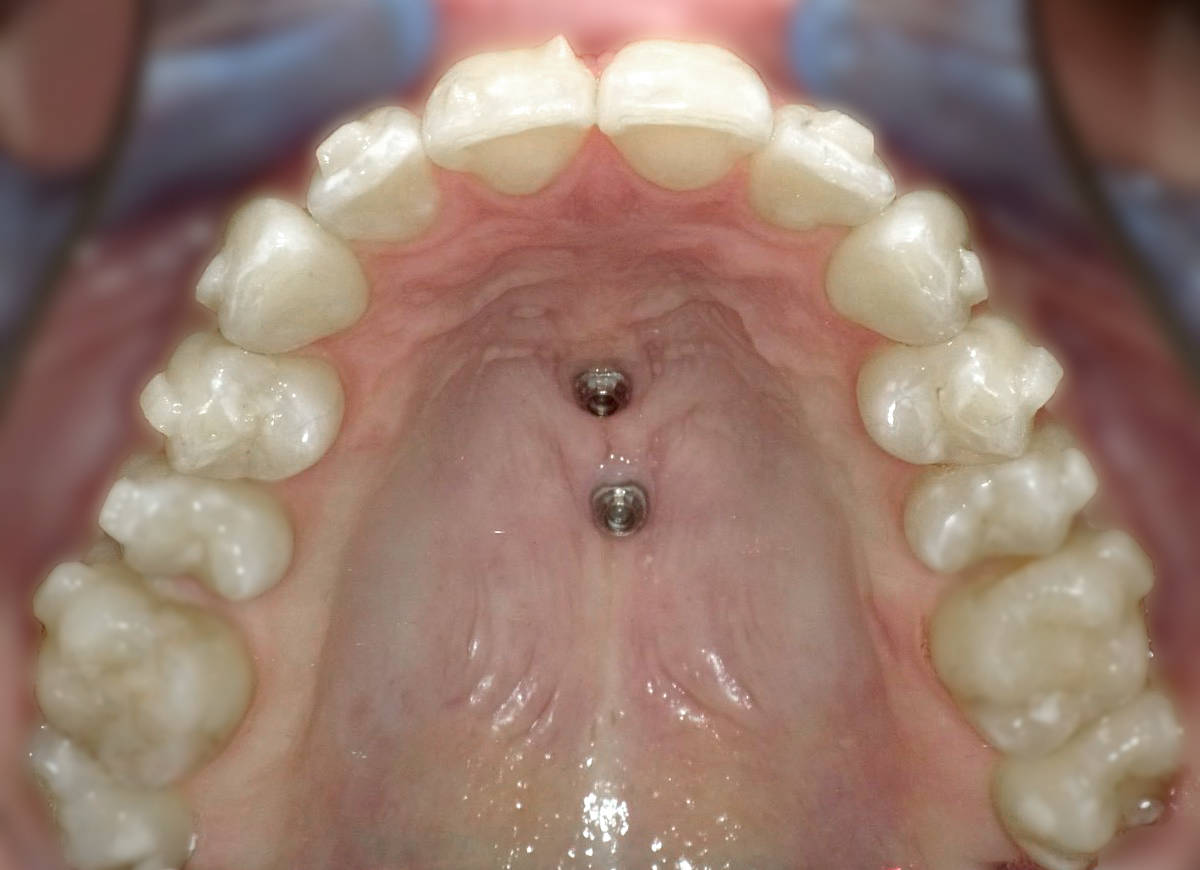

Bei PINs (engl. “Stift“) handelt es sich um Minischrauben, die unter örtlicher Betäubung der Mundschleimhaut im Kieferknochen befestigt werden. Dadurch lassen sich zum Beispiel Apparaturen mit Außenbögen (Headgear) vermeiden, da im Mund mit Hilfe der PINs mehr Verankerungsmöglichkeiten geschaffen werden. Kleine Zug- oder Druckfedern oder kieferorthopädische Drähte können daran befestigt und mit der Zahnspange verankert werden.

PINs werden übrigens auch TADs (Temporary Anchorage Device) genannt, denn sie bleiben nur für eine bestimmte Zeit im Mund und werden dann wieder entfernt.